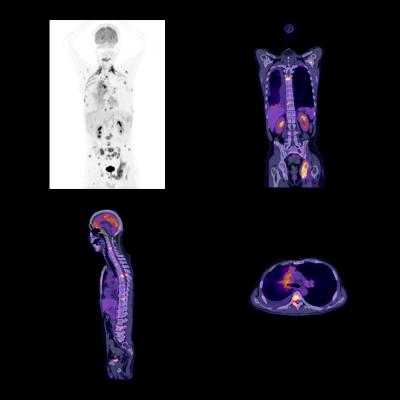

September 13, 2017 — Blue Earth Diagnostics announced the upcoming oral presentation of initial results from the FALCON clinical trial of fluciclovine (18F) positron emission tomography/computed tomography (PET/CT) at the 2017 American Society for Radiation Oncology (ASTRO) annual meeting Sept. 24-27 in San Diego. The FALCON trial evaluated the impact of F-18 PET/CT on patient management in biochemically recurrent prostate cancer patients scheduled for salvage radiation therapy treatment with curative intent. Trial results will be presented by Eugene Teoh, M.D., Oxford University Hospitals NHS Trust, Oxford, U.K.